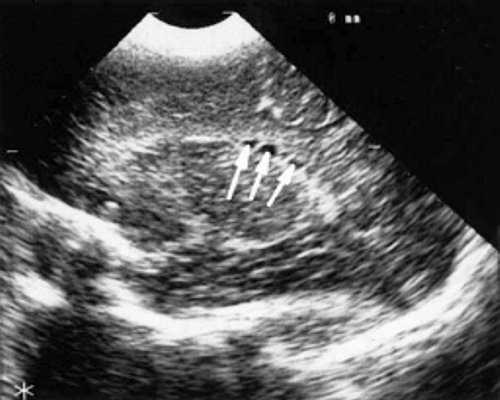

При эхоэнцефалографии у детей I группы выявлено от 1 до 3 изолированных кистозных структур (не сочетающихся с другими структурными изменениями) диаметром от 0,2-0,5 см (рис. 1, 2), расположенных в верхушке или теле сосудистого сплетения левого бокового желудочка. У 3-х из этих детей исходные данные вентрикулометрии соответствовали нормальным значениям. У 1-го ребенка отмечено незначительное (до 0,6 см) расширение межполушарной щели и субарахноидальных пространств по конвекситальной поверхности мозга и умеренное симметричное увеличение ширины лобных рогов (преимущественно) и высоты тел боковых желудочков (до 0,7 см).

Рис. 2. Эхоэнцефалограмма ребенка Д. с цитомегаловирусной инфекцией, 2-е сут. жизни. Стрелками обозначены кисты в теле сосудистого сплетения левого бокового желудочка.